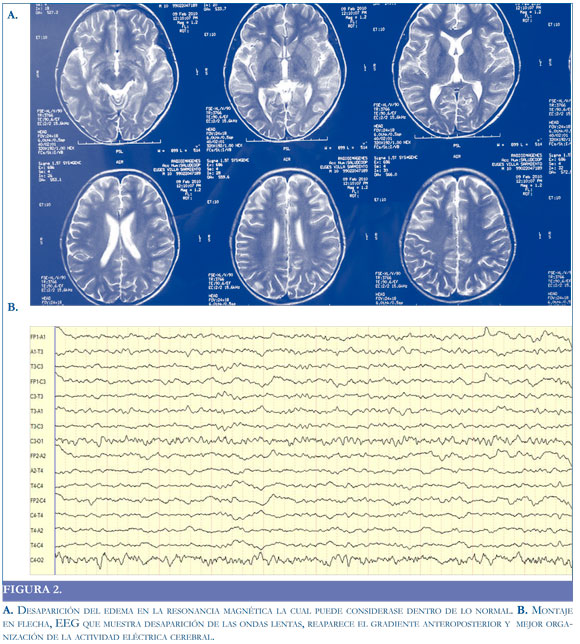

Se realizó RM, que mostró lesiones hiperintensas, afectando en forma simétrica la corteza e intersecciones fronto-temporal y parieto-occipital, con moderado borramiento de surcos; y EEG que con hallazgo sugestivo de disfunción subcortico-cortical difusa y bilateral (Figura 1).

En el presente caso, las imágenes por RM evidencian el compromiso cortico-subcortical fronto occipital secundario al edema vasogénico (16) que afecta la sustancia blanca y cuyas imágenes pueden atribuirse a loeucoencefalopatía multifocal.

Además de la resonancia, ante un paciente con signos que sugieran encefalopatia o encefalitis, el EEG tiene gran importancia al demostrar la disfunción de la actividad eléctrica cerebral (cortical o subcortical) y su progresión.

Los hallazgos electroencefalográficos en pacientes con encefalitis o encefalopatía no son específicos, los más frecuentes corresponden a lentificación del ritmo de fondo, por lo que el análisis visual del electroencefalograma deber ser ordenado y orientado al estudio de las ondas lentas y debe incluir: frecuencia, morfología, localización (focal o generalizada), reac-

tividad, periodicidad y patrones particulares (17, 18).

Algunos autores sugieren que si el compromiso es cortical (sustancia gris), predomina la actividad delta polimorfa y si el compromiso es subcortical, los patrones arrítmicos son más comunes. Por lo general, la severidad del cuadro clínico se corresponde con las anormalidades registradas en el EEG (19). En el caso presentado, el EEG en la etapa aguda de la enfermedad mostró un ritmo de fondo delta, polimorfo, difuso (bilateral), no reactivo que se fue organizando en la medida en que el paciente fue mejorando clínicamente.